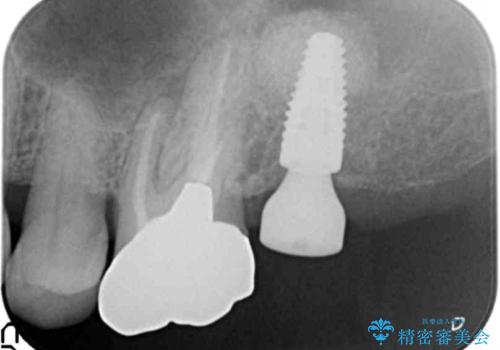

上顎洞が近接しており上顎骨の厚みが薄いことから、ソケットリフト(上顎洞底挙上術)をインプラント埋入と同時に行いました。

奥歯でしっかりと咬むことができるようになり、ご満足頂けました。

初診時から治療終了時までのレントゲンをお見せして説明差し上げたところ、「お~!骨ができている!」と喜んで下さいました。

ソケットリフトにより上顎洞底を挙上し骨造成することにより、骨の厚みが薄い部分でもインプラントが可能になります。

インプラントの種類:ストローマン BLT

クラウンの種類:メタルボンドクラウン エコノミー